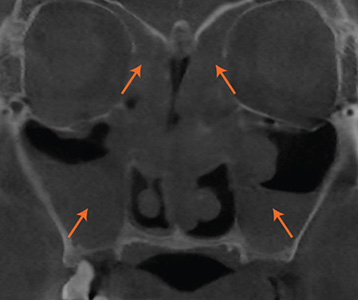

• 재수술 전

• 재수술 후

1차 수술 재발 원인 정확히 분석

완성도 높은 재수술을 위해

CT, 문진, 내시경, 후각, 음향,

통기도 검사 진행.

현재 상태를 정확히 분석합니다.